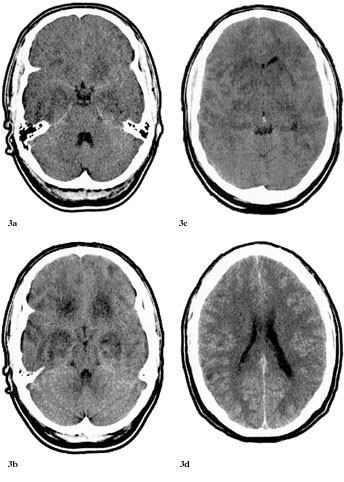

Pasienten ble overflyttet til Namdal Sykehus 6.6. Han var somnolent, desorientert og gav stereotype svar. Han hadde ingen fokale utfall. På mistanke om herpes simplex-encefalitt ble det iverksatt behandling med aciklovir 3 ⋅ 750 mg intravenøst, i tillegg fenytoin 2 ⋅ 250 mg intravenøst mot symptomatiske epileptiske anfall. Dagen etter ble pasienten soporøs. EEG var preget av en generalisert langsom aktivitet, delvis i form av bilateral synkron, rytmisk deltaaktivitet (frontal intermittent rhythmic delta acitvity, FIRDA). CT viste symmetriske forandringer i basalgangliene og basale deler av cerebrum som var ødematøs (fig 2a, 2b). En ny spinalvæskeprøve, tatt 8.6., viste 17 celler. En CT fra 9.6. viste progredierende forandringer (fig 3).

Dessverre hadde vi ingen mulighet til å få utført MR og obduksjon. Likevel er en akutt demyeliniserende encefalomyelitt mindre sannsynlig på grunn av at sykdomsutviklingen ikke kom helt akutt, men var gradvis innsettende i løpet av ti dager. Dessuten hadde man ikke fokale eller multifokale motoriske eller sensible utfall (10, 13). CT-funn viste progredierende, symmetriske forandringer som gav hypodensitet først i basalganglier og senere generelt, men hele tiden mest i basale deler av storehjernen og i de limbiske strukturer (fig 1 – 3). Retrospektivt aner man allerede ved første CT-undersøkelse (fig 1b) små hypodense områder ut for 3. ventrikkel på hver side lavt i basalgangliene. Disse funnene tyder heller på en atypisk encefalitt enn på en akutt demyeliniserende encefalomyelitt og korresponderer med de kliniske funn av hukommelsesproblemer og personlighetsforandringer. Pasienten fikk terminalt sentral respirasjonsstans, noe som kan tyde på hjernestammeaffeksjon.

Sammenfattende hadde begge pasienter en sammenliknbar utvikling av de cerebrale symptomene: Nedsatt hukommelse og orientering, personlighetsforandringer, hjernestammesymptomer og generaliserte tonisk-kloniske anfall, men ingen fokale motoriske eller sensible utfall. Bildediagnostikken viste lesjoner i basalgangliene, spesielt i nucleus caudatus og limbiske strukturer, især i hippocampusområdet.